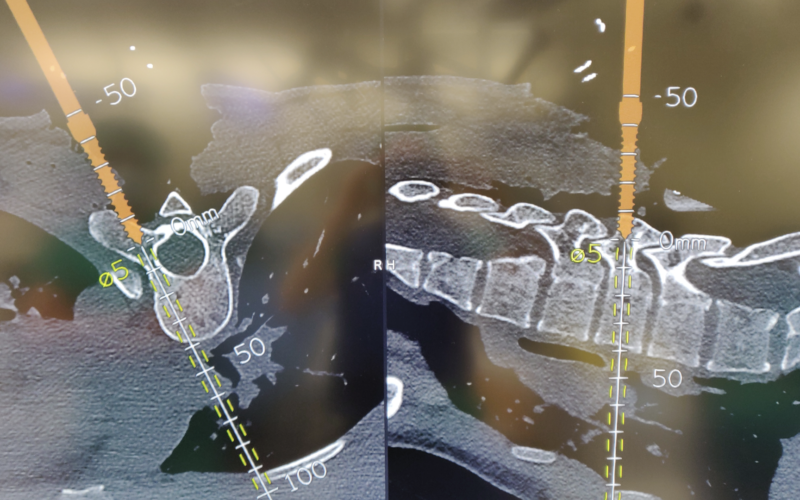

Navegación de columna

Consiste en la utilización de un “GPS o navegador” que nos indica el trayecto que deben llevar los implantes para poder situarlos de manera correcta en la columna. Con esta herramienta se optimiza la precisión de la cirugía. Es más necesario en las cirugías de más complejidad.